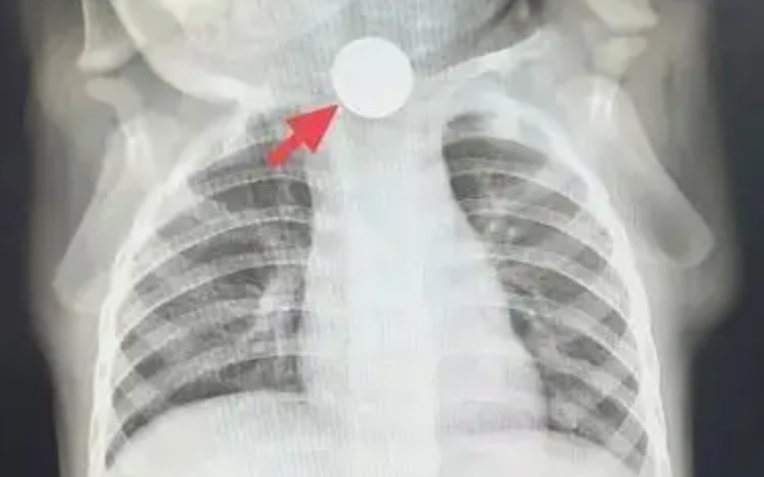

“Không thể chủ quan được, trước tiên cho bé chụp X-quang ngực để loại trừ vấn đề ở phổi!” – bác sĩ dặn gia đình. Thế nhưng, kết quả phim chụp mang lại không phải sự yên tâm, mà là một phát hiện khiến mọi người giật mình: ở đoạn trên thực quản của Đông Đông, có một đồng xu mắc kẹt!

Sự thật lập tức sáng tỏ: cái gọi là “chán ăn” thực chất là đồng xu mắc ở thực quản gây đau, khiến bé không thể ăn uống bình thường; chảy nước dãi là do dị vật chặn lại, nước bọt không nuốt xuống được; ho là phản xạ khi nước bọt tràn vào đường thở. Chẩn đoán trước đó là “chán ăn do ảnh hưởng tâm lý” hoàn toàn là nhận định sai lầm!

“Trẻ bị mắc một đồng xu trong thực quản đã gần một tuần, cần chuẩn bị nội soi lấy dị vật ngay!”. Sau khi nhận được thông báo khẩn, ê-kíp nội soi nhanh chóng vào vị trí, chuẩn bị kỹ lưỡng trước thủ thuật. Khi ống nội soi dạ dày được đưa vào, có thể thấy rõ đồng xu mắc ngang trong thực quản. Vùng niêm mạc xung quanh đã bị viêm đỏ, sưng phù, thậm chí xuất hiện ổ loét sâu, liên tục rỉ máu. Các bác sĩ thao tác hết sức cẩn trọng, chính xác gắp lấy đồng xu. Toàn bộ quá trình diễn ra trong không khí căng thẳng nhưng trật tự, cuối cùng đồng xu cũng được lấy ra thành công. Nhìn đồng xu vừa được gắp ra, bố mẹ Đông Đông vừa đau lòng vừa nhẹ nhõm, liên tục nắm tay bác sĩ cảm ơn.